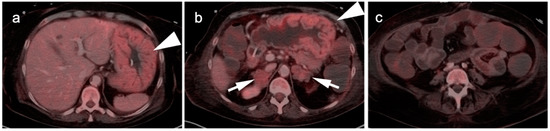

7. Adrenal Cancer